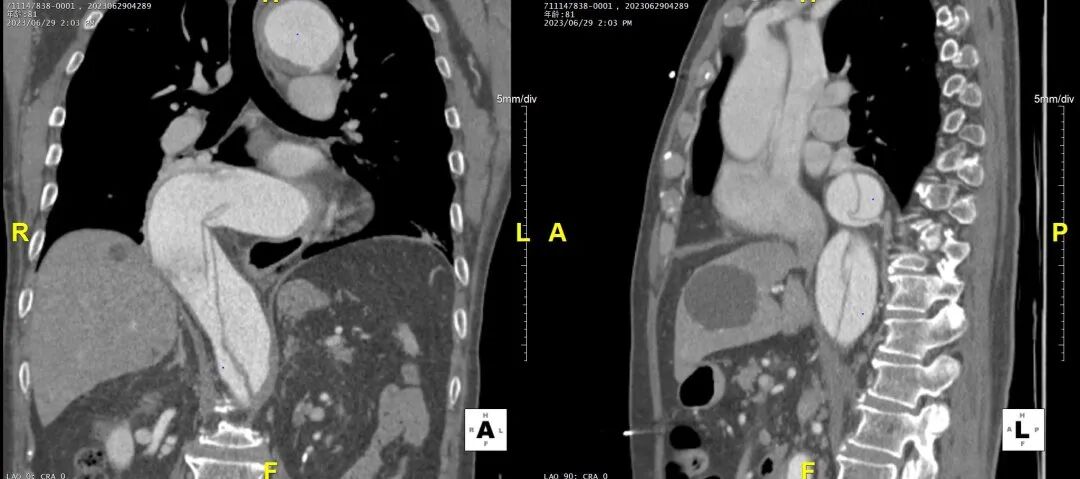

病例CTA详解

3D影像

1)内膜多处撕裂,真腔严重狭窄。

2)CA假腔供血,SMA双腔供血,LRA假腔供血,RRA真腔供血,腹主段闭塞。

3)LSA起始部平均直径43mm+,降主段多发破口,真腔狭窄。